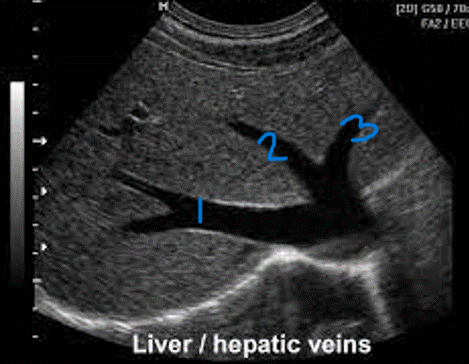

<p>In this sagittal plane, what is #1?</p>

In this sagittal plane, what is #1?

<p>In this sagittal plane, what is #2?</p>

In this sagittal plane, what is #2?

<p>In this sagittal plane, what is #3?</p>

In this sagittal plane, what is #3?